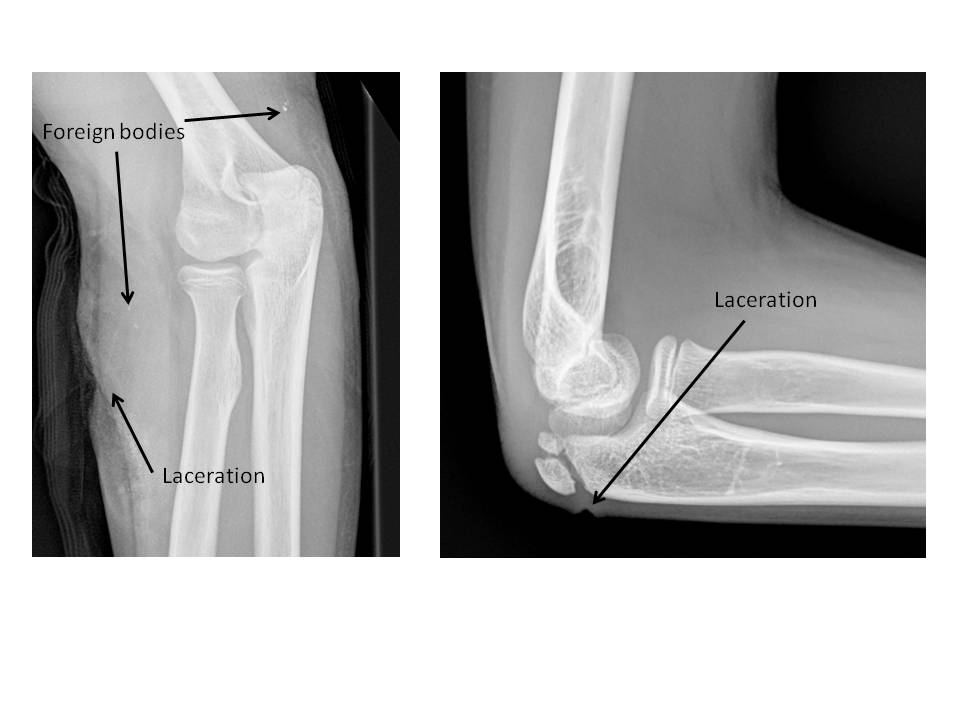

Soft Tissues